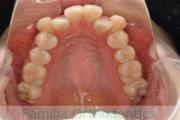

出っ歯とかみ合わせを治したいとのことで小学生の時に来院されました。一期治療ではリップバンパーのみで経過を観察し、中学生の時に再診断をしました。やや叢生(でこぼこ、ガタガタ)がきつめでしたが、拡大・非抜歯・マルチブラケット法にて治療を行いました。二期治療は、2年半、30回の通院が必要でした。

非抜歯治療を行いましたので、後戻りのリスクが高めですので、保定観察が重要です。